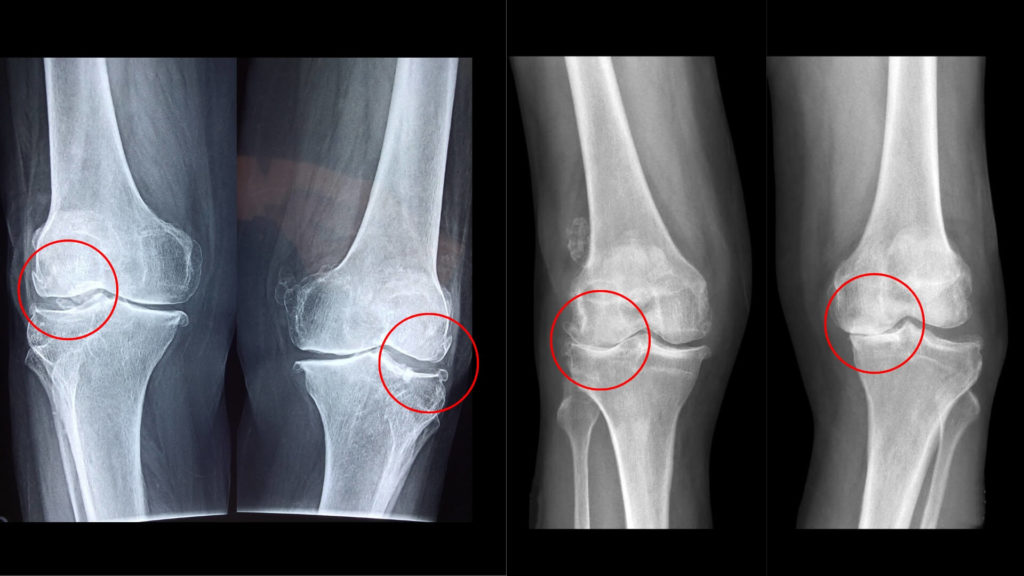

上記のレントゲン写真は変形性膝関節症の症状です。皆タイプが異なっています。

左は外側の半月板が損傷し内側の関節の隙間がなくなってしまい内側の下に骨棘ができてしまっています。

左中央は外側にも骨棘が形成し内側の隙間がなくなってしまっています。

右中央は膝関節の隙間が全体的になくなってしまい、特に外側で膝の摩擦が強く影響しています。

右は内側の関節面がくっついてしまい摩擦力が強くかかりさらに大きく関節のずれが出てしまっています。

症状は個人差があり、痛みや状態も異なっているので、このように画像が確認できるとより明確に対応することができます。